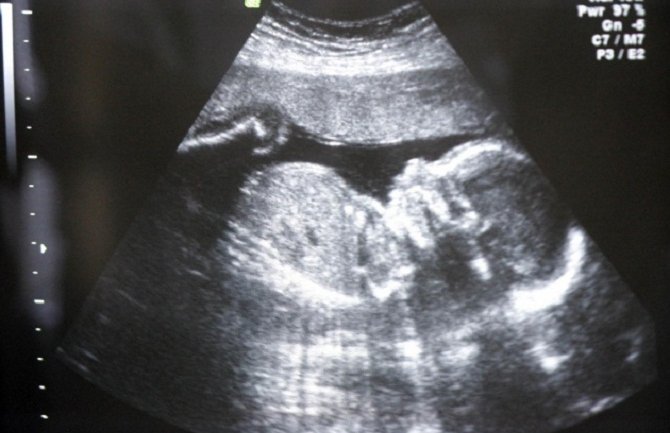

Sadašnji zakon dozvoljava abortus u prvih 14 nedjelja trudnoće

Kao i većina drugih zemalja Evrope, sadašnji španski zakon dozvoljava abortus u prvih 14 nedjelja trudnoće, a novopredloženi zakon omogućava prekid trudnoće jedino u slučajevima silovanja ili ukoliko je drugo stanje žene opasnost za njeno zdravlje, što mora biti dokazano medicinskom dokumentacijom, prenijela je agenciaj Rojters.